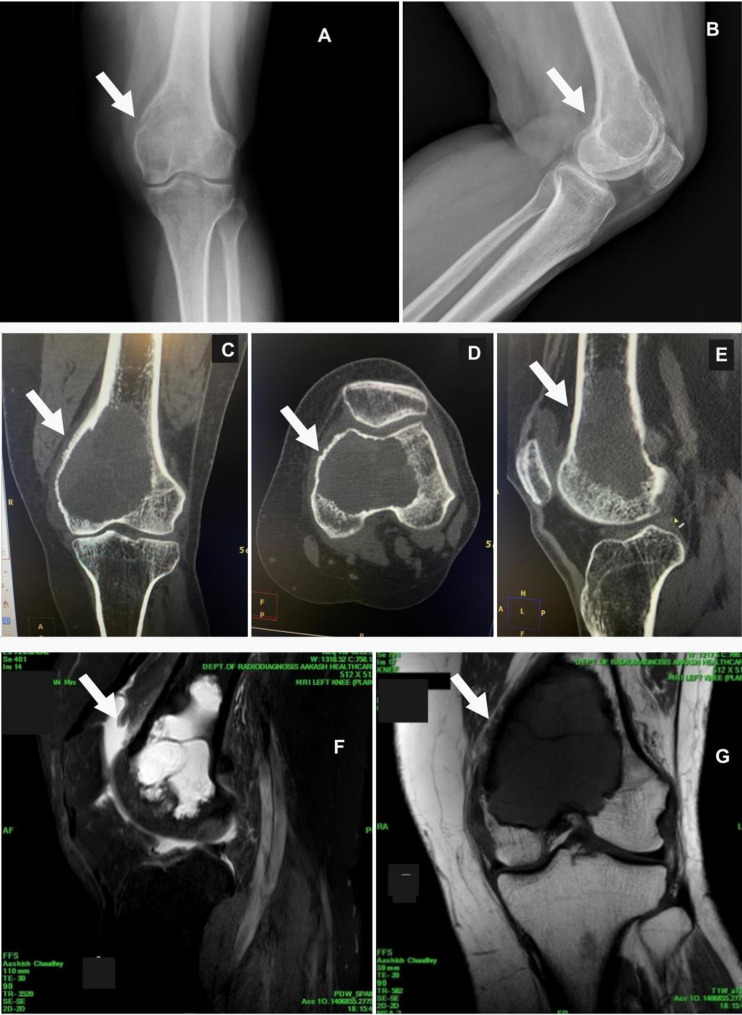

Reconstruction of a large distal femoral giant cell tumor using a 3D-printed condylar support lattice metal implant and fibular grafts: a novel biomechanical and surgical approach.